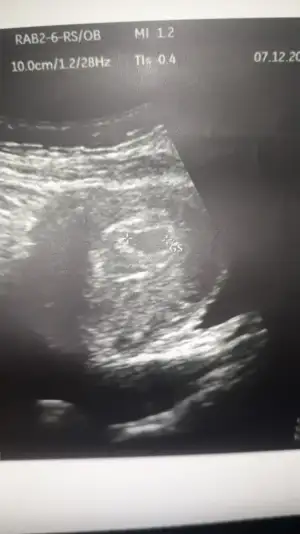

Kuzum hamileyim 😍😍 ilk gebeligim dusuk fln olmadi

• IMG-20201201-WA0036.webp

IMG-20201201-WA0036.webp

72,8 KB · Görüntüleme: 90

• IMG-20201207-WA0010.webp

IMG-20201207-WA0010.webp

22,5 KB · Görüntüleme: 87